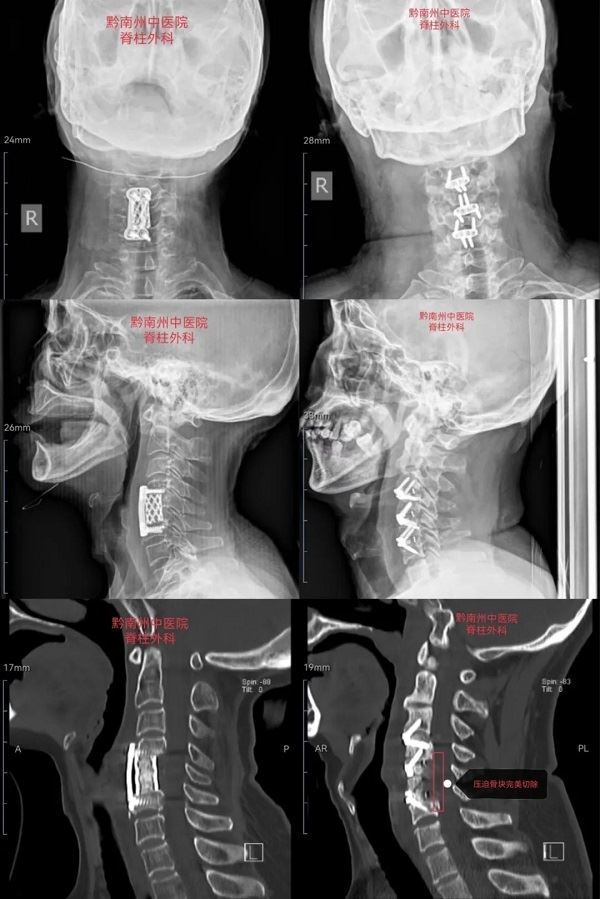

颈前路椎体X型截骨融合术(Anterior cervical X-shape-corpectomy fusion,ACXF),是颈椎前路传统手术术式之一的颈前路椎体次全切融合术进行的改良。该术式通过将病人自体切除的骨块进行回植重建,避免使用异体金属物质进行重建,从而减少了金属物质所产生的相关术式并发症(如金属形状不合适、金属位置改变、金属钢板断裂),提高了骨融合率,同时避免切除太多骨块导致的疼痛、出血和感染等手术并发症。

原术式术后影像 改良术式术后影像